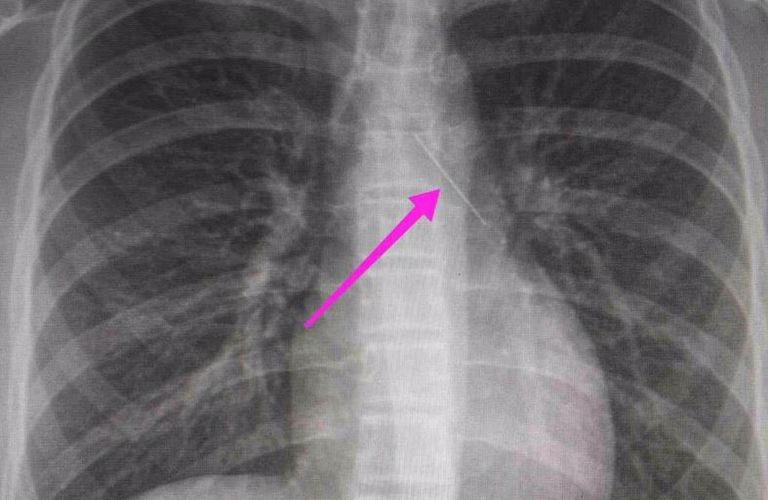

Από την απεικονιστική διερεύνηση που πραγματοποιήθηκε με ακτινογραφία θώρακος αρχικά και ακολούθως με αξονική τομογραφία θώρακος, διαπιστώθηκε η ύπαρξη αιχμηρού μεταλλικού ξένου σώματος στην αναπνευστική οδό (αριστερός κύριος βρόγχος) και όχι στην πεπτική οδό.

Η ανήλικη υπεβλήθη σε βρογχοσκόπηση και διαπιστώθηκε η μετακίνηση και ενσφήνωση της καρφίτσας στον δεξιό κύριο βρόγχο. Μετά οπό εργώδεις προσπάθειες ολοκληρώθηκε με επιτυχία η αφαίρεσή της.

Το κορίτσι μεταφέρθηκε αμέσως στο νοσοκομείο και οι γιατροί εντόπισαν αρχικά την καρφίτσα στον αριστερό βρόγχο, στον αυλό που οδηγεί στον πνεύμονα. Όταν όμως έγινε η βρογχοσκόπηση, βρέθηκε στον άλλον βρόγχο.